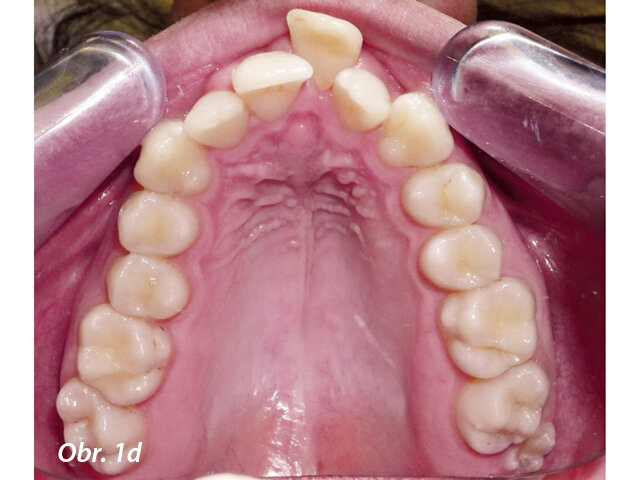

17letý chlapec přišel na konzultaci v prosinci 2014. Při intraorálním vyšetření bylo zjištěno: vztah molárů v I. třídě dle Anglea oboustranně a vztah špičáků v I. třídě vlevo a II. třídě vpravo. Šířka horního zubního oblouku v úrovni molárů byla normální, v místě premolárů však byl zubní oblouk výrazně zúžený a v mezišpičákové oblasti bylo výrazné stěsnání. V dolním zubním oblouku (úzký, tvar paraboly) bylo stěsnání s úplným deficitem místa pro zub 42, který byl v ektopické lingvální poloze. Hloubka skusu byla stoprocentní s traumatickým nákusem do gingivy v okolí dolních frontálních zubů. Zuby horního oblouku byly mírně větší než průměr, s malým nepoměrem Boltonova indexu. Objektivní extraorální vyšetření odhalilo syndrom dlouhého obličeje, vývoj střední třetiny obličeje byl normální a nazální pyramida byla široká ve spojení s mírnou mandibulární retruzí (obr. 1a–h).